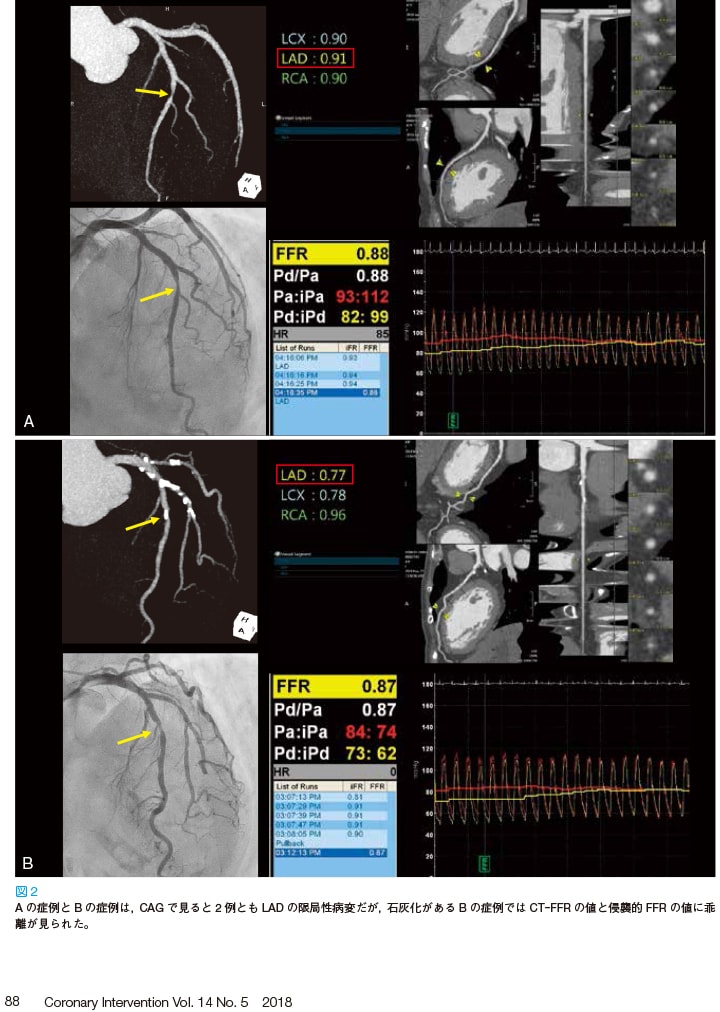

血管撮影装置をバージョンアップ

血管撮影装置をバージョンアップし、さらなる”被曝低減”と、一歩先の”治療支援システム”を実現。

当クリニックでは、現在稼働中の血管撮影装置2台のバージョンアップを行いました。

バイプレーン装置には、冠動脈疾病の血管内治療術を支援するライブイメージガイダンスの包括的システムソリューション”PCI Suite”を導入しました。

これまでは不可能であった治療中のライブ画像に血管の動画像をオーバーレイする機能(Dynamic Coronary Roadmap)や、また、高速画像強調処理技術によってステントの視認性をリアルタイムに向上させる機能(Live StentBoost)が加わり、新たな治療支援画像として威力を発揮しています。

また、iFR Roadmapは、Dynamic Coronary Roadmapの機能を強化し、複雑な狭窄病変の治療を、iFR値を参照しながら行えるシステムで、治療の必要な部位をより詳細に評価することができます。

一方、シングルプレーン装置では、より被曝低減が行えるArullaClarity FD10へバージョンアップしました。

我々は、これらの最新技術を地域の皆様に還元できるよう、今後も努力して参ります。

Dynamic Coronary Roadmap

Live StentBoost

iFR Roadmap